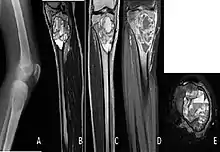

A. X-ray: osteolytic lesion in tibia near knee. B/C/D/E. MRI with E showing fluid levels.

The cause is unknown.[1] Diagnosis involves medical imaging.[1] CT scan and X-ray show lytic expansion lesions with clear borders.[1] MRI reveals fluid levels.[1]

X-ray and CT scan show lytic expansion lesions with clear borders.[1] Expansion of cortex gives the lesion a balloon-like appearance. Larger lesions may appear septated.[11] MRI reveals fluid levels.[1] Bone scan shows outer radiotracer uptake, with a central dark area.[1][11]